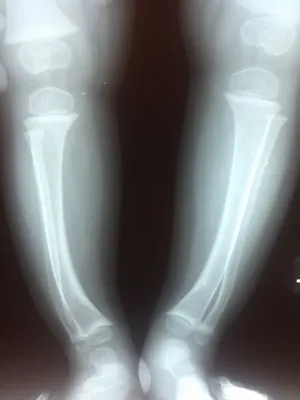

X-rays are taken of the entire lower extremity. The metaphysial diaphysial angle is measured. This represents the degree of deformity that is present in the upper inner portion of the lower leg bone (tibia). Changes indicative of growth plate disturbances may be seen. When x-rays are taken early they allow an accurate assessment of the deformity and an assessment of its progression.

Xrays of Bow Legs in toddler (Below)

Knock knee position is demonstrated (left), and the bowleg position is also pictured (right).